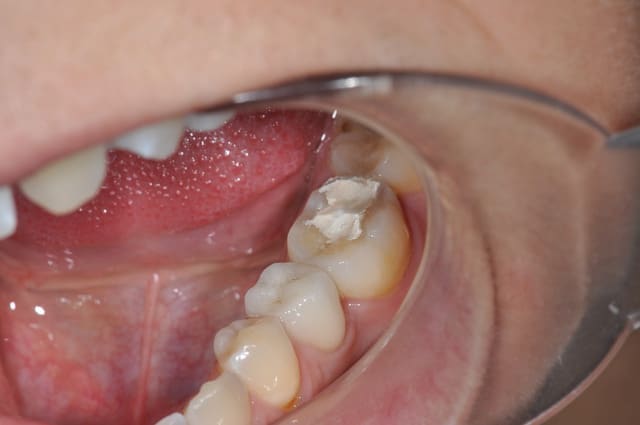

sur cette dent vous faites bio + inlay

T'as pas autre chose, une photo sans le pansement, une radio, une photo des autres dents ?

Ce qui m'interpelle c'est que j'ai l'impression qu'on voit la dentine sur la face occlusale, est-ce que toutes les dents sont comme ça ?

car mise en sous-occlusion ^^

37 semble aussi abrasée, donc je soupconne une abrasion et des parafonctions

légère mise en sous-occlusion effectivement

Je privilégierai l'inlay sauf si ça le fait pas une fois la carie nettoyée.

Il y a de bonnes parois dentaires, ça me ferait mal au coeur de les supprimer.

Pourquoi avoir placer en sous occlusion comme cela ?

L'émail perdu complique un peu l'inlay-onlay.